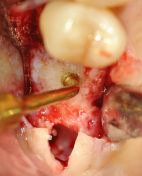

OSTEOTOMIA PIEZOELETTRICA DEL PAVIMENTO DEL SENO MASCELLARE, RIALZO DI 4MM

Con la preparazione ultrasonica del sito implantare si può percepire la resistenza corticale del pavimento del seno mascellare per poi eroderlo con OT4 diamantato e sollevare il seno